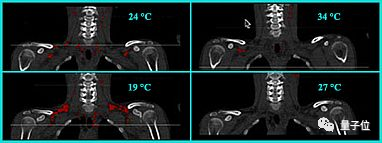

在这个研究中, 研究对象为5名健康男性,平均年龄21岁,这些人白天进行常规活动,然后每天晚上回到房间,研究时间长达4个月,每个月房间温度设置分别为:24℃、19℃、24℃、27℃。

最终的实验结果是,在暴露于轻度寒冷(19℃)一个月后,参与者的棕色脂肪量增加了42%,脂肪代谢活动增加了10%。(下图红色部分为棕色脂肪)

恢复到正常温度(24℃)后,这些变化又恢复至原来的水平。

而在最后一个月温度略高(27℃)的环境下,所有的变化又完全逆转。

△图源:Diabetes